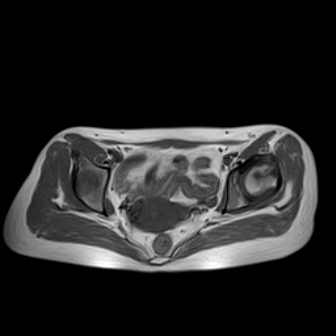

请看看我的片子,我得的什么病,该怎么治疗?谢谢[img][/img]

片子不全,应该是左侧股骨头无菌坏死,右侧似乎没问题,到正规医院治疗,千万别看广告去小医院,吃中药什么的,都是骗人的(说了也白说,百分百都得让人骗点钱才甘心。)

应该是左侧股骨头无菌坏死